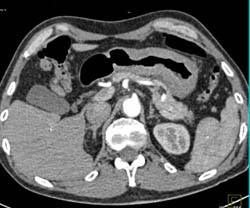

Linitis Plastica